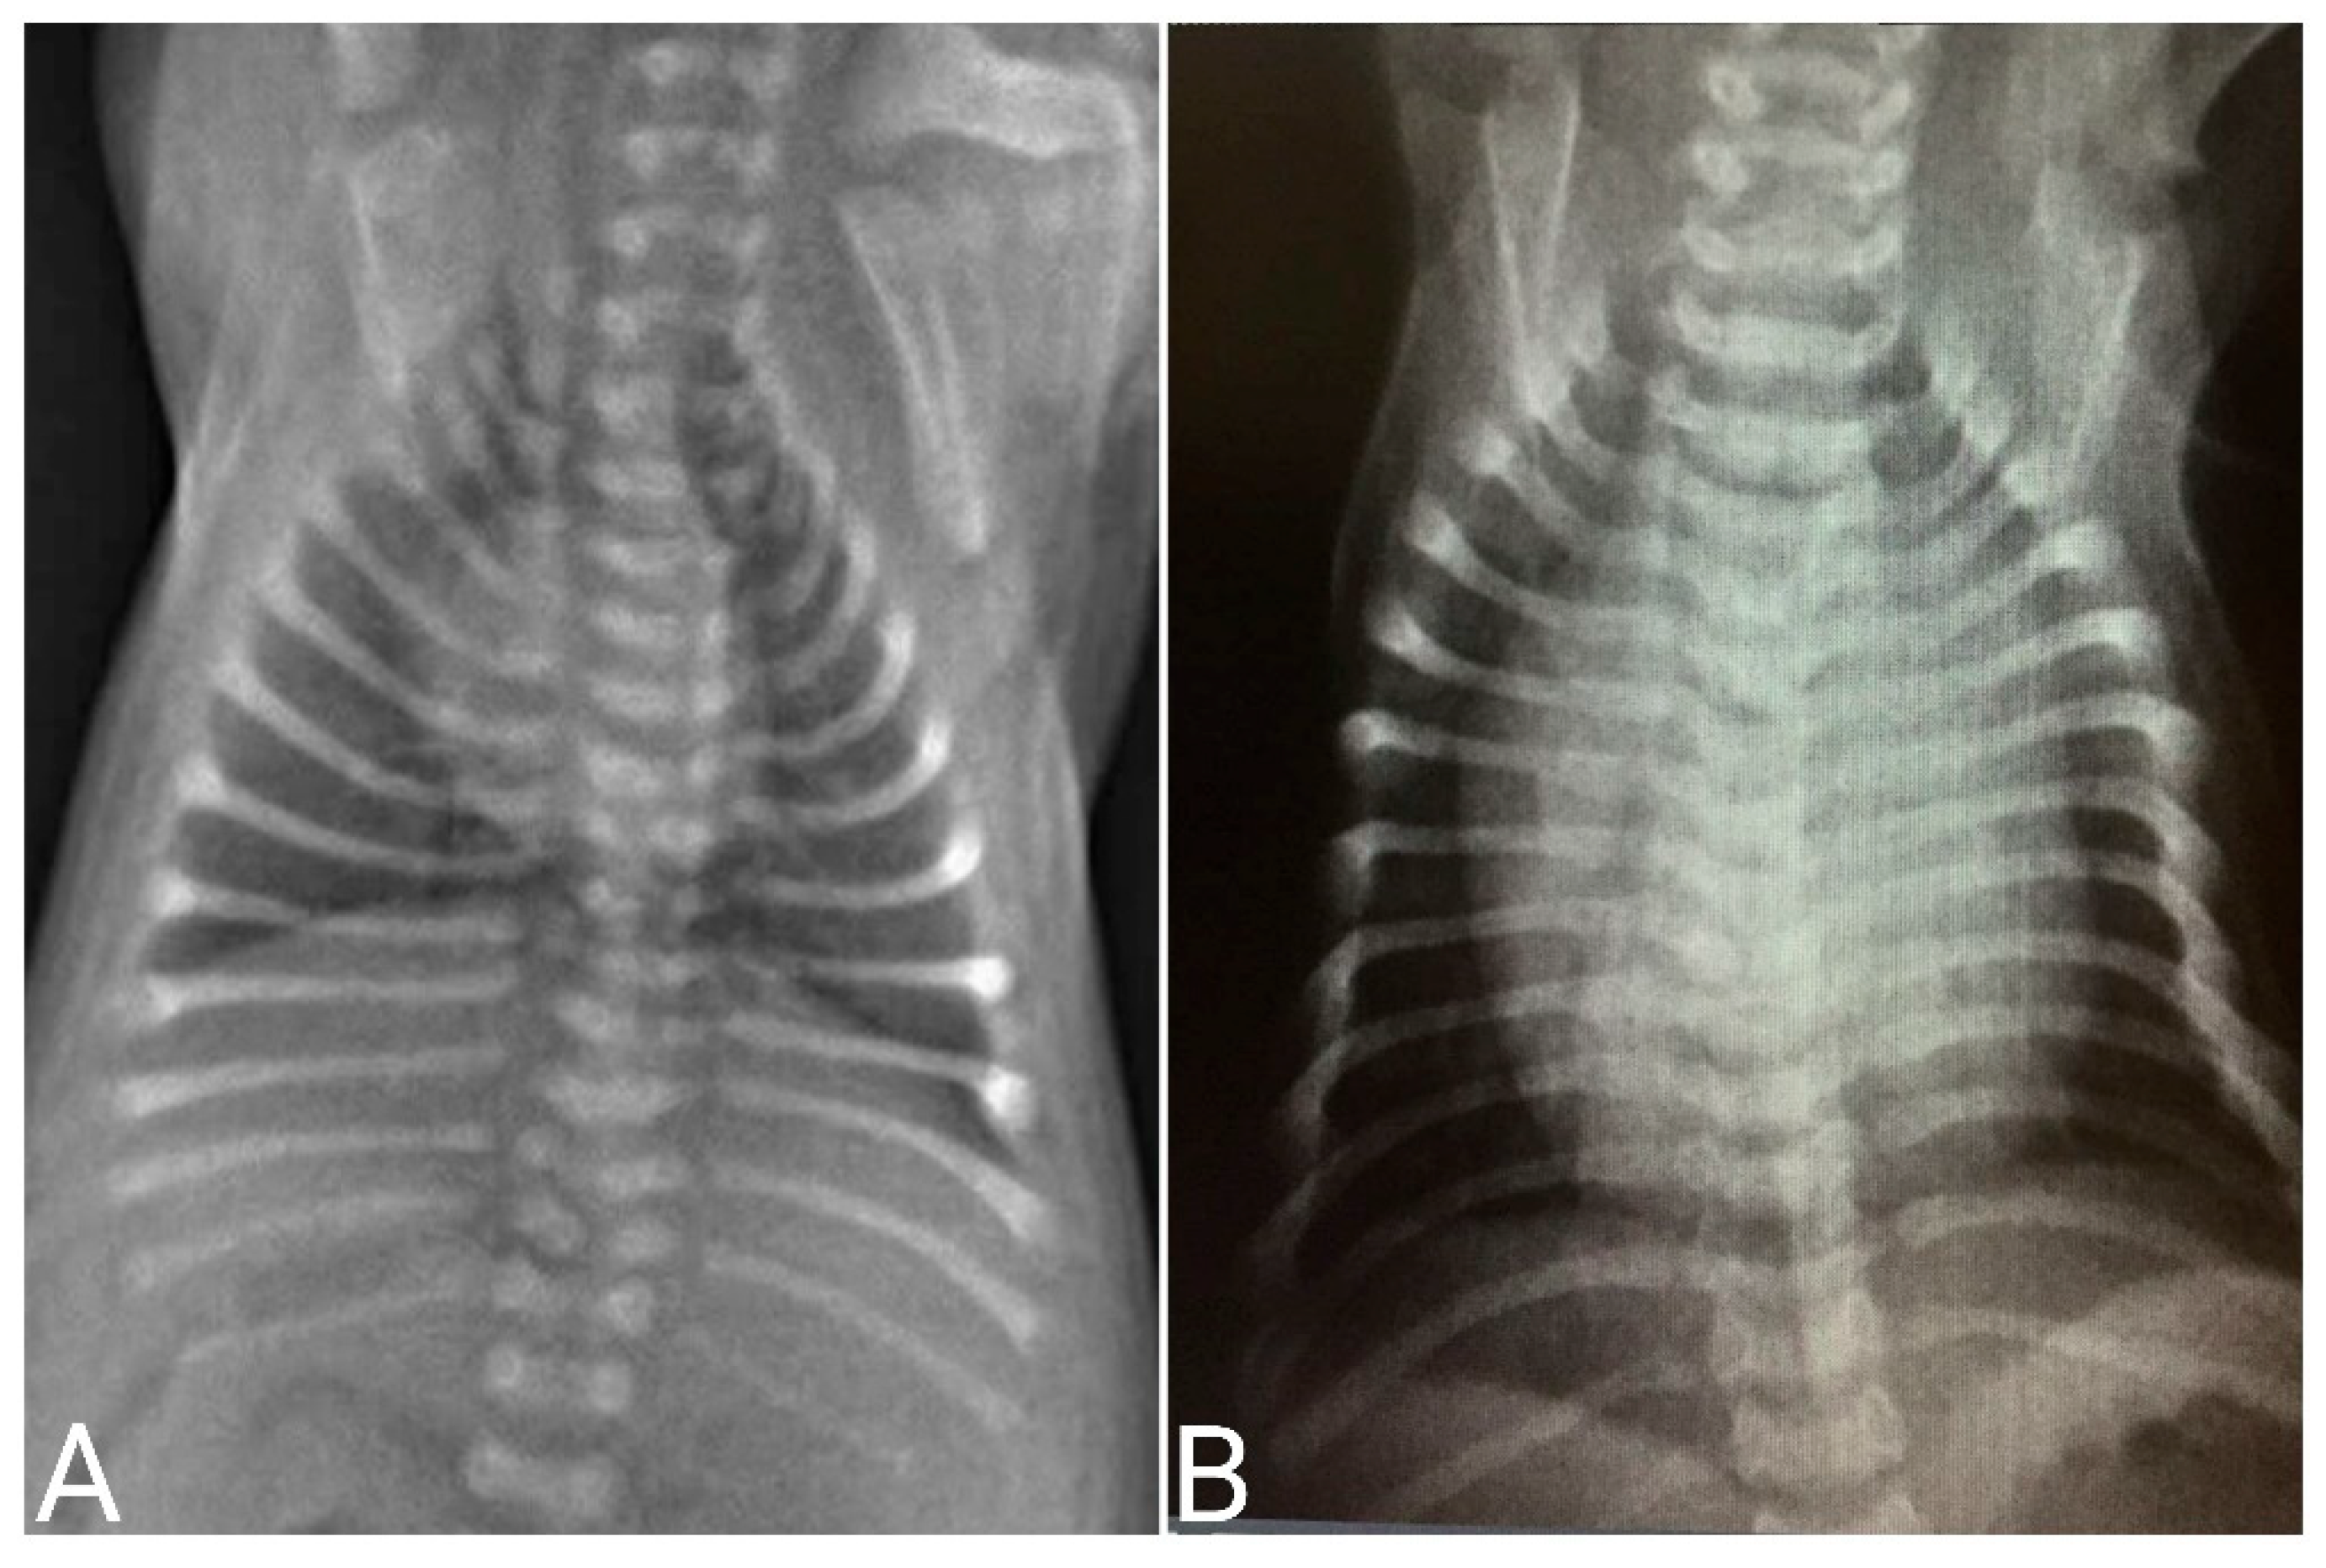

Radiographic Examination